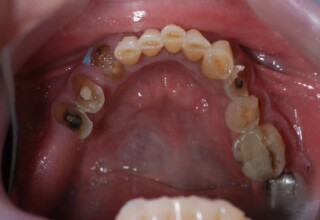

Εκτεταμένη αποκατάσταση με στεφάνες(θήκες) σχεδόν σε όλα τα δόντια λόγω εκτεταμένων αποτριβών, παλαιών αποκαταστάσεων, οπισθίων απονευρώσεων και αισθητικών προβλημάτων. Ο ασθενής(60 ετών) παρουσίαζε έντονο βρυγμό (τρίξιμο δοντιών) που δεν είχε αντιμετωπίσει ποτέ, με αποτέλεσμα μεγάλες αποτριβές που απειλούσαν την ακεραιότητα των οπισθίων δοντιών. Οι ανασυστάσεις(σφραγίσματα) των δοντιών έγιναν κυρίως με συγκολλούμενα ρητινώδη υλικά και τρεις χυτούς άξονες ψευδοκολοβώματα. Τοποθετήθηκαν προσωρινές στεφάνες όπου εκτιμήθηκε το επιθυμητό μέγεθος, το σχήμα και η θέση των δοντιών πριν κατασκευαστούν οι τελικές μόνιμες στεφάνες.